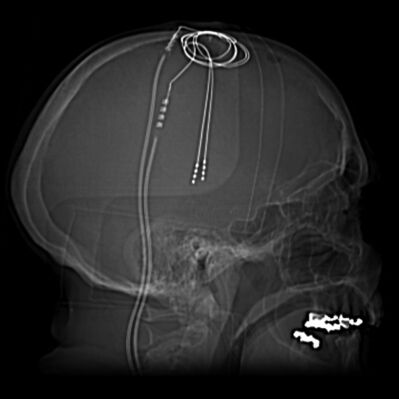

Die Tiefe Hirnstimulation (THS) wird zunehmend zur Behandlung von Parkinson und anderen Bewegungsstörungen eingesetzt. Diese Behandlungsmethode beinhaltet die Implantation von Elektroden in tiefe Hirnstrukturen, die mit einem Stromversorgungsgerät verbunden sind. Das Gerät ähnelt einem Herzschrittmacher und wird in die Brust implantiert. Es kann sowohl von Ärzten als auch vom Patienten ferngesteuert und angepasst werden.

Die Stimulationsparameter werden von einem Computer gesteuert, um Amplituden, Frequenzen und Impulsbreiten anzupassen. Häufige Ziele für THS bei Parkinson sind der Nucleus subthalamicus, der Globus pallidus interna und der ventrale intermediäre Kern des Thalamus.

Neue Entwicklungen, wie richtungsweisende THS-Elektroden, helfen, die Stromausbreitung auf Strukturen zu vermeiden, die Nebenwirkungen verursachen könnten. Die Kontrolle des Stroms zu einzelnen Kontakten auf einer THS-Elektrode ermöglicht es, das elektrische Feld zwischen mehreren aktiven Kontakten zu formen. Diese Fortschritte machen THS zu einer effektiven Behandlungsoption.

Der operative Eingriff selbst umfasst mehrere Schlüsselschritte:

Dieser operative Eingriff ist komplex und erfordert ein multidisziplinäres Team von Neurochirurgen, Neurologen, spezialisierten Krankenschwestern und manchmal Neuropsychologen. THS bietet keine Heilung von Parkinson, sondern ist eine Möglichkeit, Symptome zu managen und zu lindern, insbesondere wenn Medikamente nicht mehr ausreichend wirksam sind.